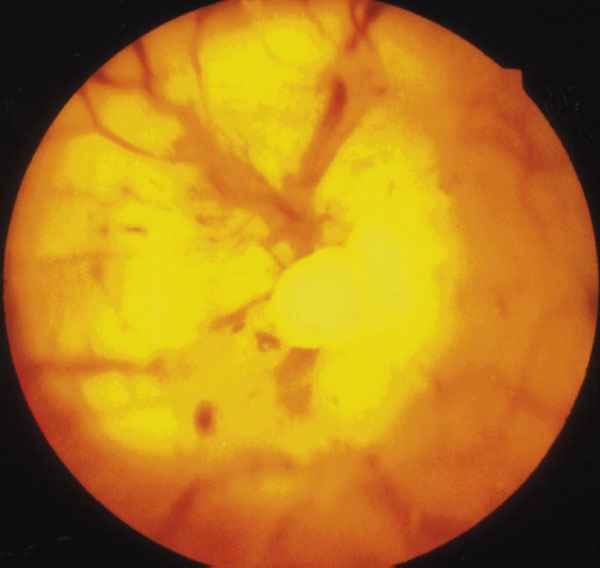

Figura 2

DETALE DEL N.O. DEL OI.